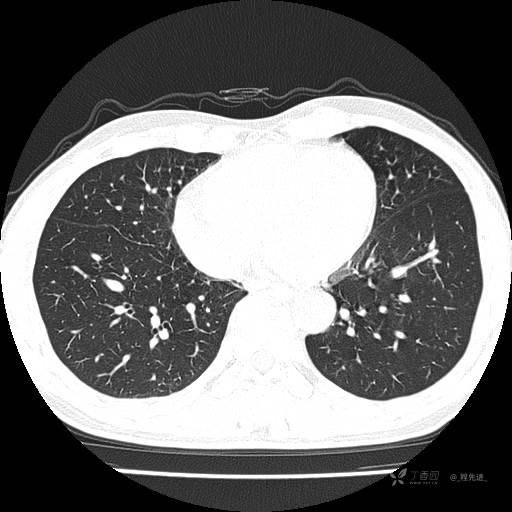

辅助检查:我院门诊胸部CT示:如下。心电图:窦性心律;正常心电图。